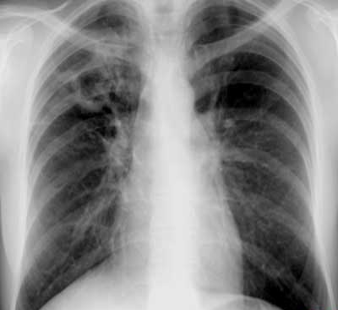

Rx toracică, incidență P-A

DESCRIERE:

pe tot teritoriul pulmonar, bilateral → opacități nodulare multiple de dimensiuni variabile, intensitate medie-mare, omogene, cu contur net

distribuție anarhică

blocuri adenopatice la niv. hilurilor pulmonare

DX: MTS pulmonare hematogene

DD:

hidatidoză - dimensiuni mai mari

bronhopneumonie - contur neregulat, neomogene, distribuție bazală